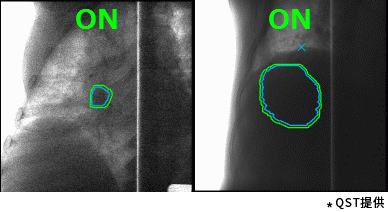

東芝的重離子癌癥放射治療系統(tǒng)具有高速3D掃描,患者自動(dòng)定位,小型化重離子旋轉(zhuǎn)機(jī)架(搭載東芝自研超導(dǎo)磁鐵實(shí)現(xiàn)重量和體積的大幅縮?。┑炔町惢夹g(shù)。實(shí)時(shí)成像的呼吸門控是照射技術(shù)與重復(fù)掃描技術(shù)的結(jié)合,能夠?qū)Π殡S呼吸運(yùn)動(dòng)的腫瘤進(jìn)行快速、準(zhǔn)確的照射,且保證劑量分布均一性。特別是,東芝憑借自身先進(jìn)的超導(dǎo)技術(shù)的加持,使旋轉(zhuǎn)機(jī)架得以逐漸小型化。這一成果直接推動(dòng)了重離子旋轉(zhuǎn)機(jī)架的商業(yè)化普及。應(yīng)用旋轉(zhuǎn)機(jī)架治療,可從360度任意角度進(jìn)行照射,避開正常組織和危及器官。治療過程中一次定位,避免了移動(dòng)患者造成的內(nèi)部臟器位移,實(shí)現(xiàn)精準(zhǔn)治療,同時(shí)提高治療效率,增加治療人數(shù),在同類型產(chǎn)品中獨(dú)具技術(shù)優(yōu)勢(shì)。

高速掃描+呼吸門控照射(動(dòng)圖) |